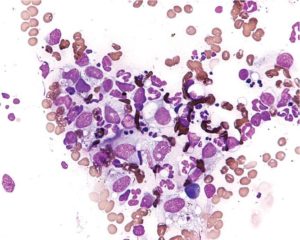

Далее образец биоматериала отправляется в лабораторию, где его окрашивают (метод Грама) и исследуют под микроскопом. В некоторых случаях может потребоваться дополнительная диагностика: мазок из зёва и носовой полости (при подозрении на стафилококк), общие анализы крови и мочи.

Чаще всего у женщин используется простой мазок. Забор материала для исследования проводится из 2 или 3 точек: слизистая заднего свода влагалища, шейки матки и иногда уретры.

Биоматериал наносится на стерильные стёкла и изучается под микроскопом. При необходимости делается посев на питательные среды с определением чувствительности к антибиотикам.